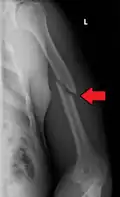

Middle

Middle fractures are usually caused by either physical trauma or falls. Physical trauma to the humerus shaft tends to produce transverse fractures whereas falls tend to produce spiral fractures. Metastatic breast cancer may also cause fractures in the humerus shaft.[12] Long spiral fractures of the shaft that are present in children may indicate physical abuse.[5]

Definitive diagnosis of humerus fractures is typically made through radiographic imaging. For proximal fractures, X-rays can be taken from a scapular anteroposterior (AP) view, which takes an image of the front of the shoulder region from an angle, a scapular Y view, which takes an image of the back of the shoulder region from an angle, and an axillar lateral view, which has the patient lie on his or her back, lift the bottom half of the arm up to the side, and have an image taken of the axilla region underneath the shoulder.[9] Fractures of the humerus shaft are usually correctly identified with radiographic images taken from the AP and lateral viewpoints.[12] Damage to the radial nerve from a shaft fracture can be identified by an inability to bend the hand backwards or by decreased sensation in the back of the hand.[5] Images of the distal region are often of poor quality due to the patient being unable to extend the elbow because of pain. If a severe distal fracture is suspected, then a computed tomography (CT) scan can provide greater detail of the fracture. Nondisplaced distal fractures may not be directly visible; they may only be visible due to fat being displaced because of internal bleeding in the elbow.[7]